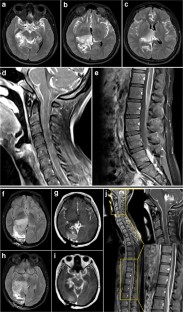

A 15-year-old girl after 1 week of symptoms was found to have a T2/FLAIR-hyperintense and contrast-enhancing thalamic mass accompanied by leptomeningeal enhancement along the entire neuraxis. Initial infectious workup was negative, and intracranial biopsy was inconclusive. Spinal arachnoid biopsy revealed an H3K27M-mutant lesion with glioneuronal features, classified thereafter as DMG. She received craniospinal irradiation with a boost to the thalamic lesion. Imaging 1-month post-radiation demonstrated significant treatment response with residual enhancement at the conus.